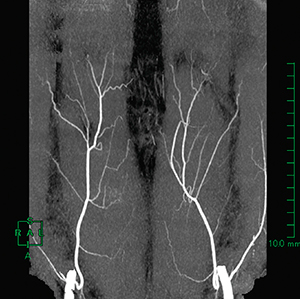

こんな画像ができればよいらしい。

| 腹直筋のとこの細かい血管:インナビネット様から転載 |